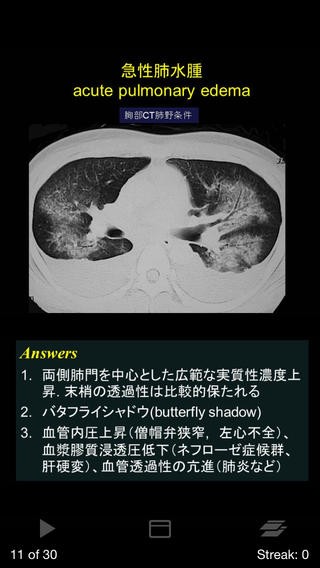

2.胸部60分基礎トレ(720円)

引用元:https://itunes.apple.com/jp/app/id596370666?mt=8&ign-mpt=uo%3D4

肺感染症や、新血管病変などの、胸部の代表的な30疾患の画像に対するQ&Aが、

全6章、60ページにわたって収録されています。